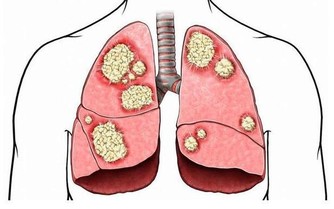

方銳華解釋,腳氣,即足癬,源於真菌感染。

皮炎平之類的複方軟膏,其主要成分是激素,激素並不能治愈真菌感染,反而還可能擴大感染面積,加重病情。